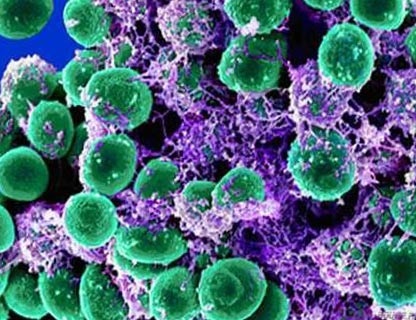

Fig. 4. Bacteriile care populează gura: mutanții Streptococcus (verde). Bakteroides gingivalis, cauzând periodontita (lila). Candida albicus (galben).

Fig. 10. Staphylococcus epidermidis parazit pe pielea oricărei persoane. Aceasta afecteaza aproape toate organele corpului uman. Aceasta cauzează mai mult de 100 de boli.